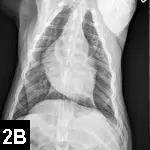

Imaging & Laboratory ResultsA peripheral catheter was placed and shock fluid therapy initiated, followed by ultrasound-guided pericardiocentesis; this resulted in immediate clinical improvement. Following stabilization, staging tests for suspected hemangiosarcoma were performed. No visible metastatic disease was identified on thoracic radiographs and abdominal ultrasound (Figure 2).

Figures 2A, 2B & 2C. Thoracic radiographs (A, B) and abdominal ultrasound (C) failed to identify any visible metastatic disease.